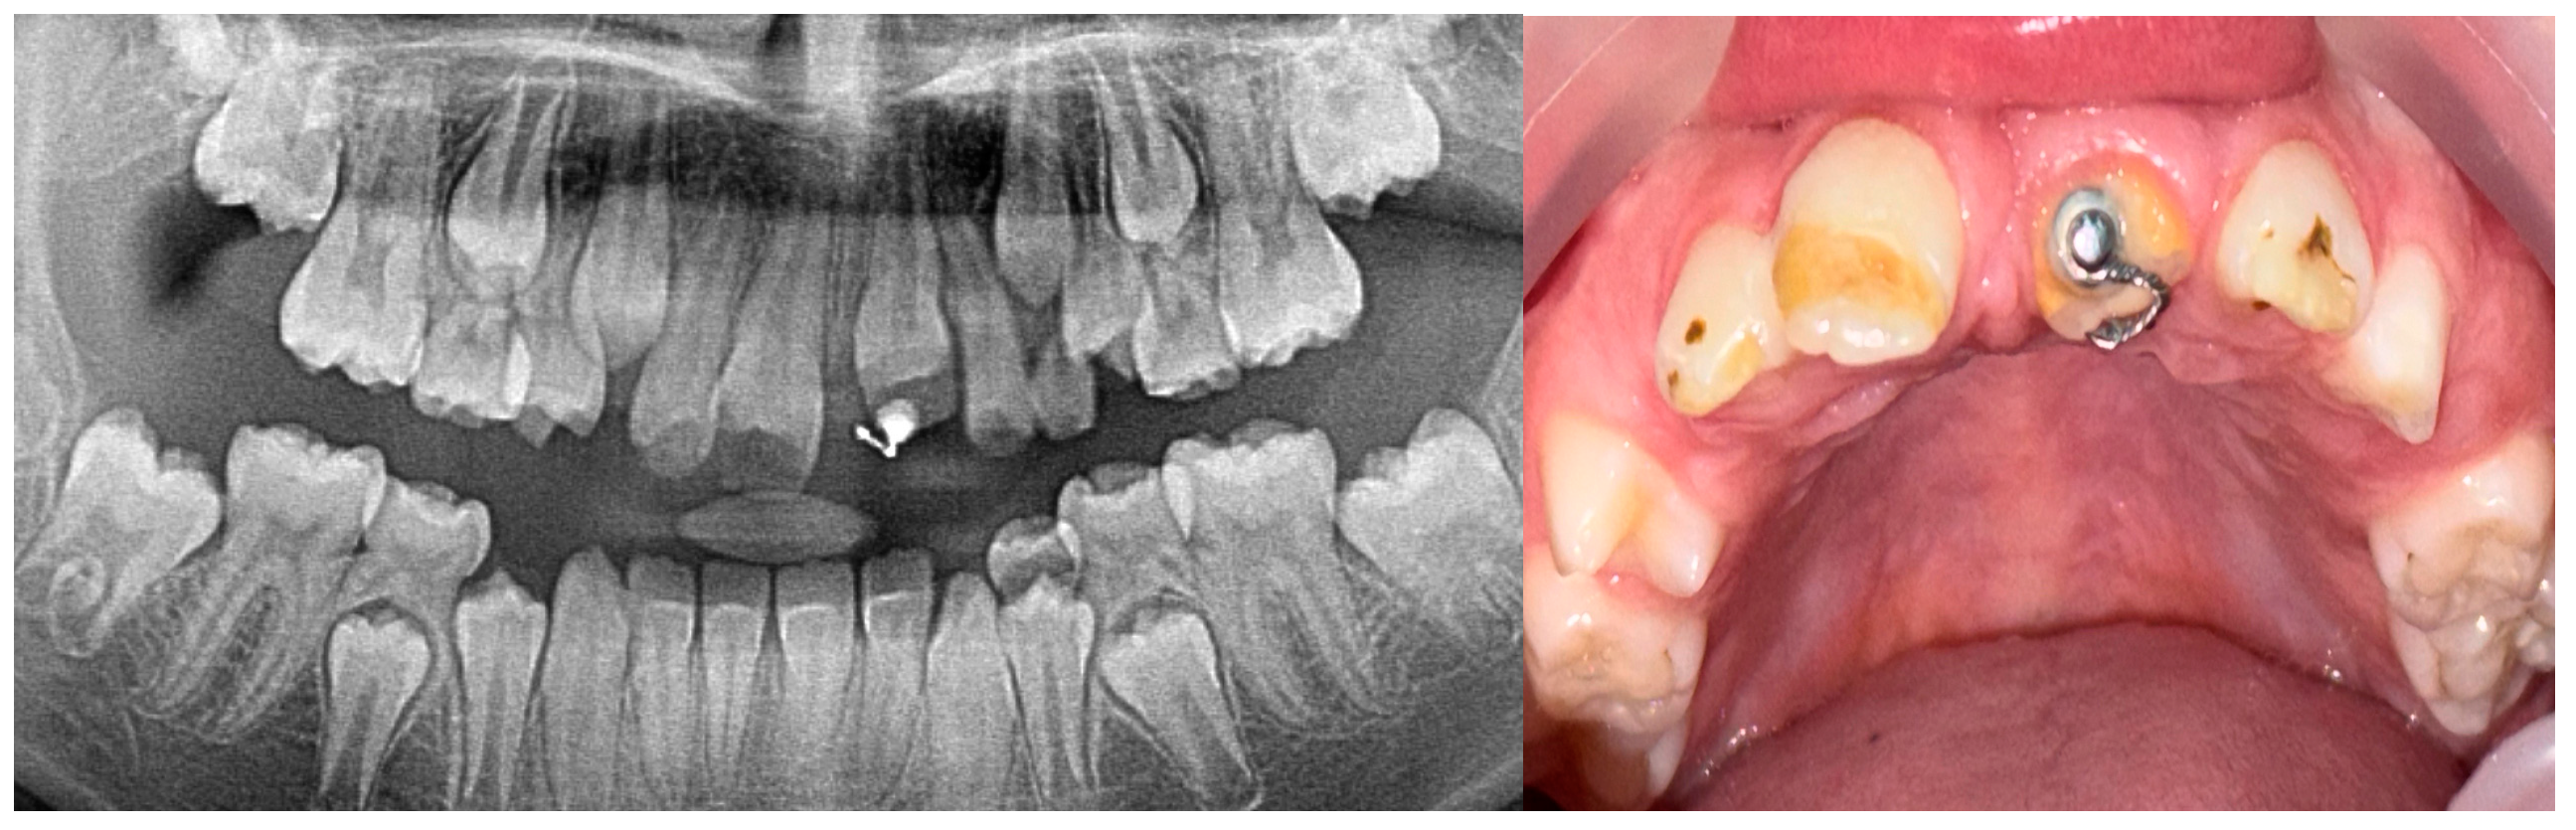

2. Case Presentation